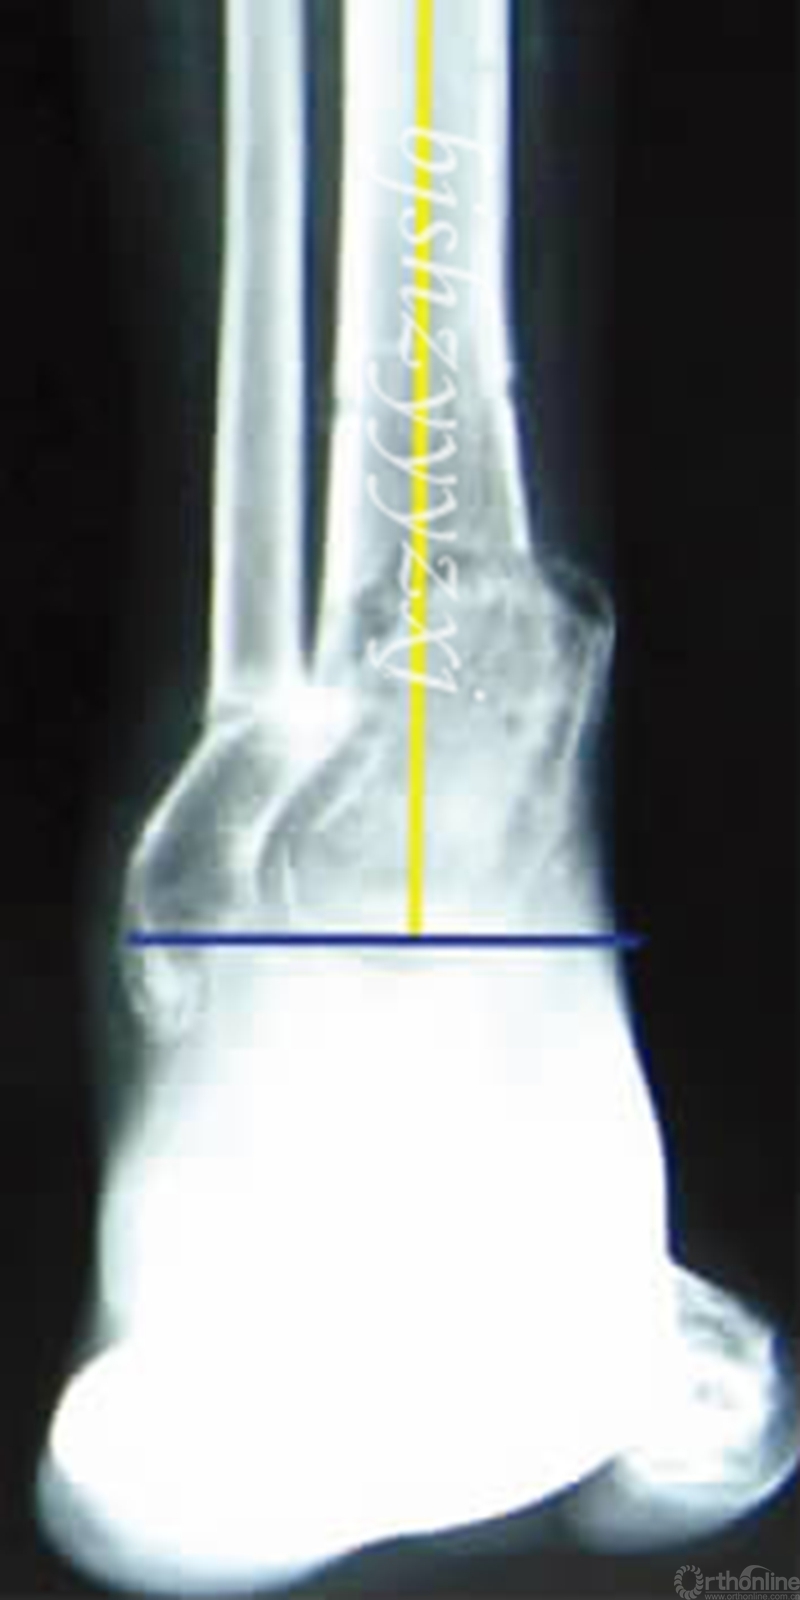

在全长片上画出下肢机械轴,可从整体判断力线,肢体长度,有无合并畸形。根据Paley提出的矫形分析原则,踝关节内翻导致下肢机械轴线内移,胫骨远端外侧角(LDTA)增大,胫骨近端和远端的解剖轴线相交于旋转成角中心(CORA),畸形顶点靠近关节面是此类畸形的特点,CORA的确定为截骨和安装外固定提供了重要参考。(见图2)

图2 在X线片上画出胫骨近端和远端的力线,相交于畸形的旋转成角中心(CORA)